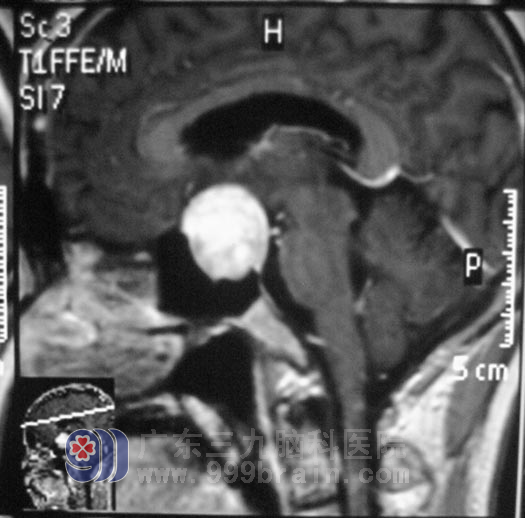

两周前,曾先生的视力下降较前明显,并伴有间断头痛,医生建议行脑部检查,头颅MR报告显示:鞍区占位性病变,考虑垂体大腺瘤,大小约28mm×27mm×30mm: